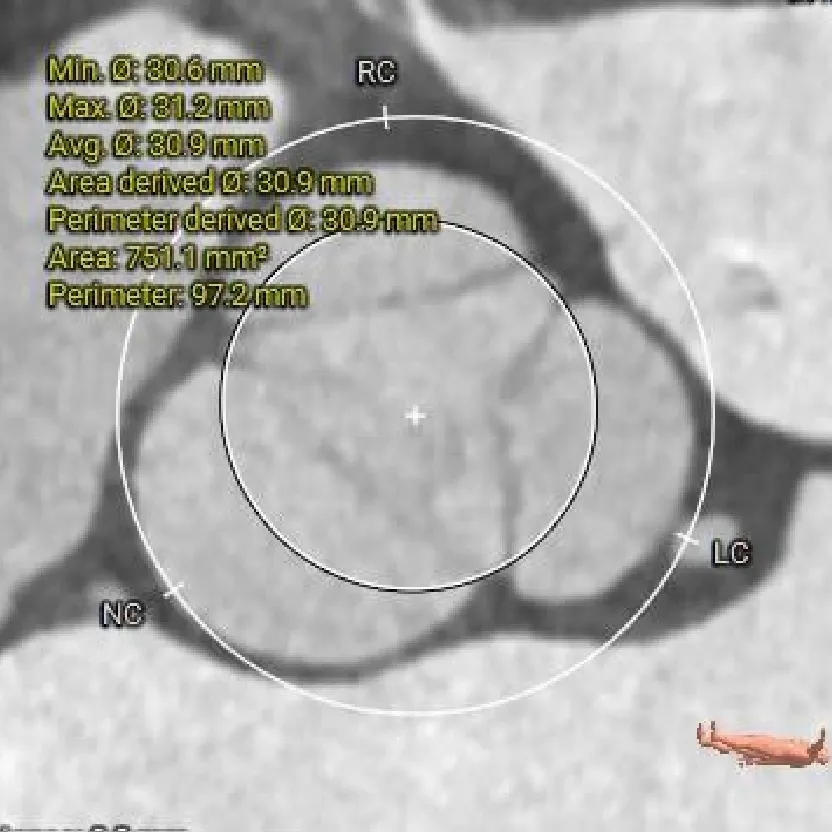

LVOT

26.2mm

瓣上结构测量

瓣上2mm

瓣上4mm

27.4mm

瓣上6mm

29.6mm

瓣上8mm

33.9mm